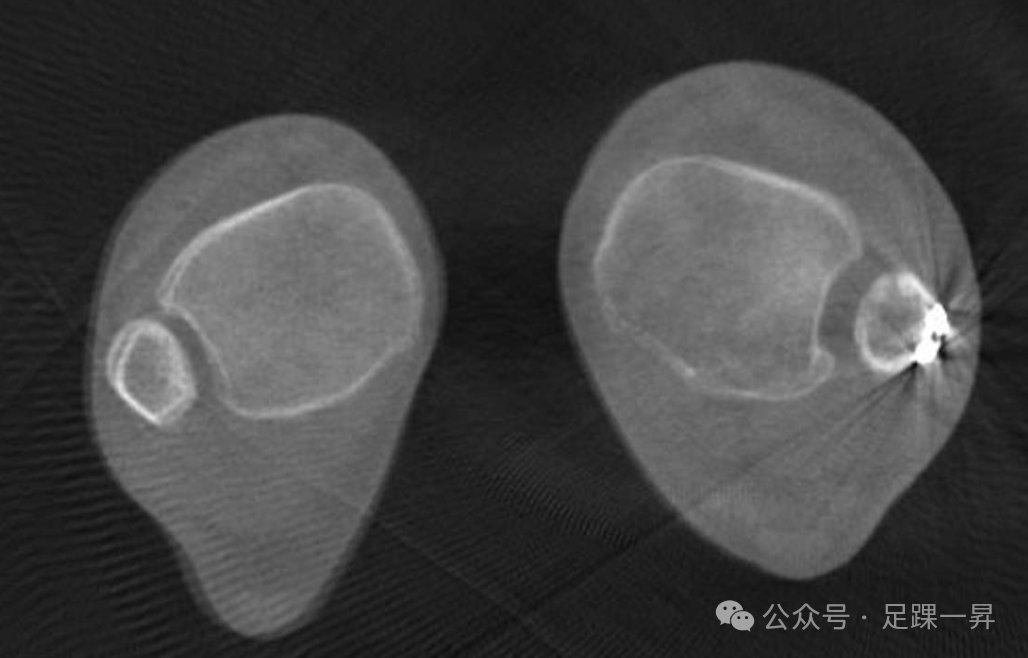

图4. 一名旋转性踝关节骨折患者的双侧负重CT图像显示,存在未固定的后踝小骨折块。后踝骨折块的畸形愈合伴外侧移位导致切迹解剖结构异常及下胫腓联合增宽。在此病例中,由于切迹解剖形态异常无法使腓骨正确就位,翻修时下胫腓联合螺钉固定的效果存疑。这凸显了即使是小的后踝骨折块也需精准处理的重要性。